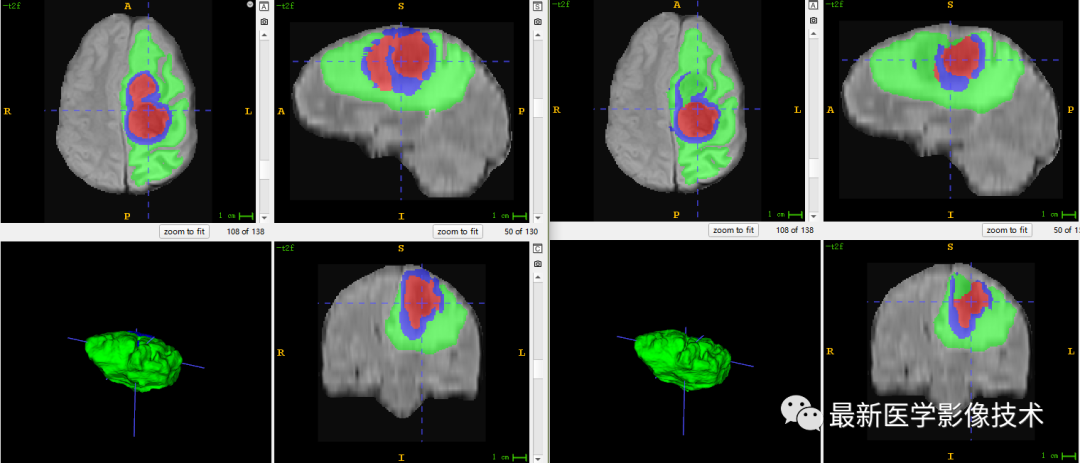

6、验证集分割结果

左图是金标准结果,右图是网络预测结果。

7、测试集分割结果